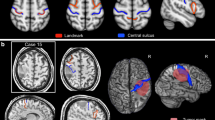

Brain plasticity is another phenomenon which may affect the fMRI results in patients with brain tumours [5, 6, 20, 26]. Fandino et al. [6] reported functional reorganization of the M1 cortex even in the unaffected hemisphere. In contrast, Ulmer et al. [26] warned against overestimating this phenomenon in pre-surgical planning. In a subgroup of patients they observed a BOLD signal reduction in close proximity of the tumour accompanied by apparently increased contralateral activation suggesting compensatory ‘pseudo-dominance’ of the homotopic M1 cortex in the healthy hemisphere. However, one third of these cases had the BOLD signal around the lesion falsely negative. We came to the same conclusion in our patient No. 1 with the contralateral cortical ‘pseudo-dominance’ (Fig. 3) in whom the functionally preserved M1 cortex adjoining the tumour was localized only by intraoperative ECS.

There have been several attempts to use the fMRI for estimating the risk of postoperative neurological deterioration. The distance between the activated BOLD cluster and the tumour was found to be a significant predictor of such deficits. Neurological deterioration occurs more likely if this distance is less than 5 mm [15]. A more conservative study [9] considered the distance of 20 mm as entirely safe. In our series, no patient in whom the areas of BOLD activation were surgically respected suffered from a worsening of their neurological state postoperatively. We consider the effort to resect a part of the precentral gyrus infiltrated by the tumour, as very risky, especially in a patient with minimal symptoms. On the other hand, if the pial border of the precentral gyrus adjacent to the tumour is spared or the tumour affecting part of precentral gyrus is well circumscribed, resection can proceed to the immediate neighbourhood of the positive stimulation cortical area (Fig. 4).

A radical resection of oligodendroglioma (grade II) located in precentral gyrus in patient No.2 A—central area demonstrating PPM on an example of cadaver dissection (patient not from this study) B—intraoperative photograph: label □ 1, 3, 4—hand movement, label □ 2—elbow flexion I—BOLD activated area (P < 0.05 FWE corrected) elicited by left hand tapping task II—preoperative T2-weighted MRI of tumour partially involving the PPM III—postoperative T2-weighted MRI